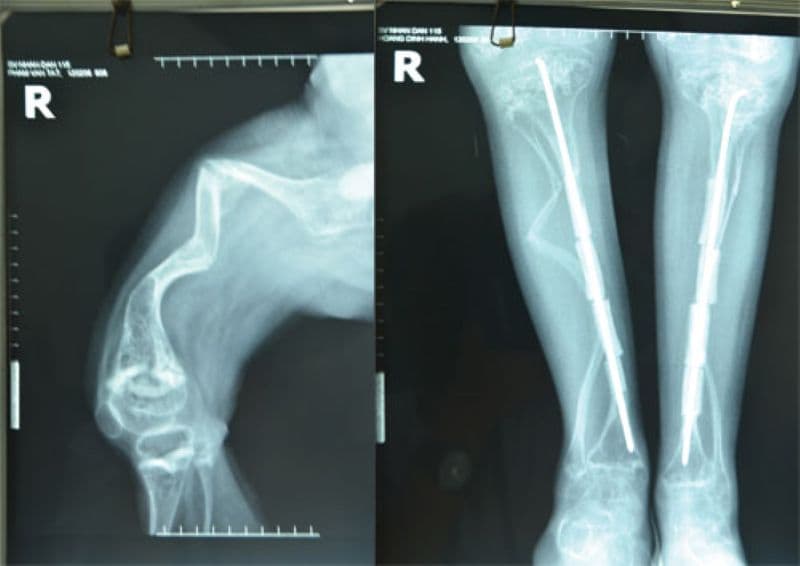

Chụp X-quang giúp bác sĩ quan sát xương gãy, biến dạng. Ở thai nhi, siêu âm thai giúp phát hiện sớm dấu hiệu gãy xương và bất thường cấu trúc. Đây là những công cụ quan trọng để đánh giá mức độ bệnh.

Đối với những trường hợp bệnh nặng, phẫu thuật chỉnh hình giúp sửa các biến dạng và cố định xương gãy, thường dùng thanh kim loại để nâng đỡ khung xương, giúp bé vận động dễ dàng hơn và hạn chế xương lệch. Song song đó, vật lý trị liệu và phục hồi chức năng rất quan trọng để tăng cường cơ bắp, cải thiện vận động và giữ sự linh hoạt. Dụng cụ hỗ trợ như xe lăn, nạng cũng giúp bé di chuyển thuận tiện hơn.